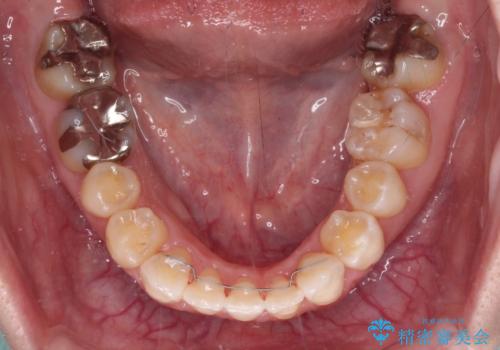

- 1年4ヶ月

骨格のズレと歯の欠損があったため、仕上がりの調整に時間がかかると思いましたが、舌突出癖の改善や顎間ゴムの装着をしっかりと行ってくださったので、速やかに治療を終えることができました。